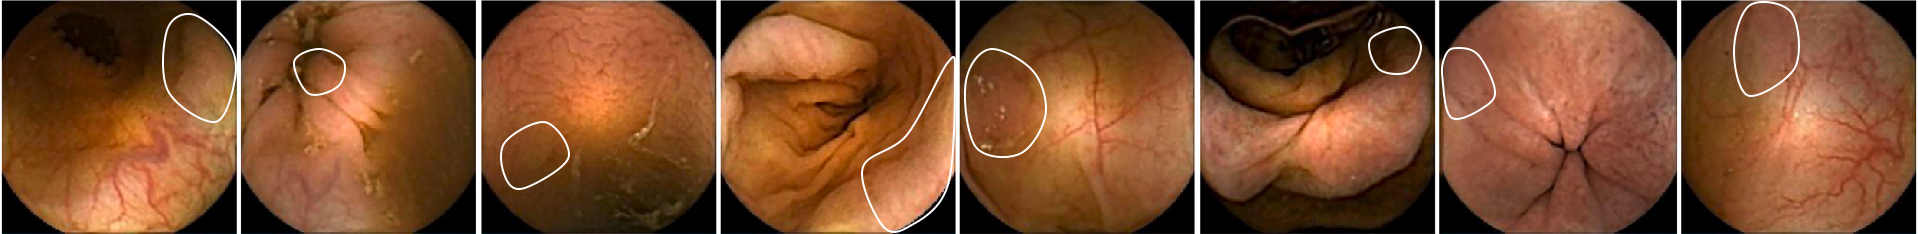

Figure 11 shows eight polyp images where the system has not obtained enough features to predict the frame as polyp. Each image shows a boundary with the location of the polyps. These difficult cases are complex to detect in single images by the system. The evaluation of a whole sequence of images where the polyp is seen facilitates detection by the human eye. Due to the complexity of polyp detection, sometimes is easier for humans to detect them through the sequence.